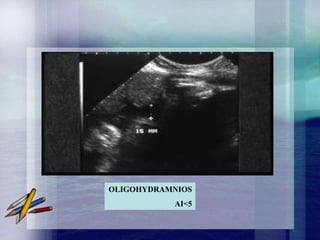

OLIGOAMNIOS

• Il s'agit d'une diminution

pathologique de la quantité de liquide

amniotique dont le diagnostic est

échographique : plus large citerne de

liquide amniotique inférieure à 2 cm

ou index amniotique des 4 quadrants

inférieur ou égal à 5 cm. Fréquence :

de 0,5 à 1%.

OLIGOHYDRAMNIOS

AI<5